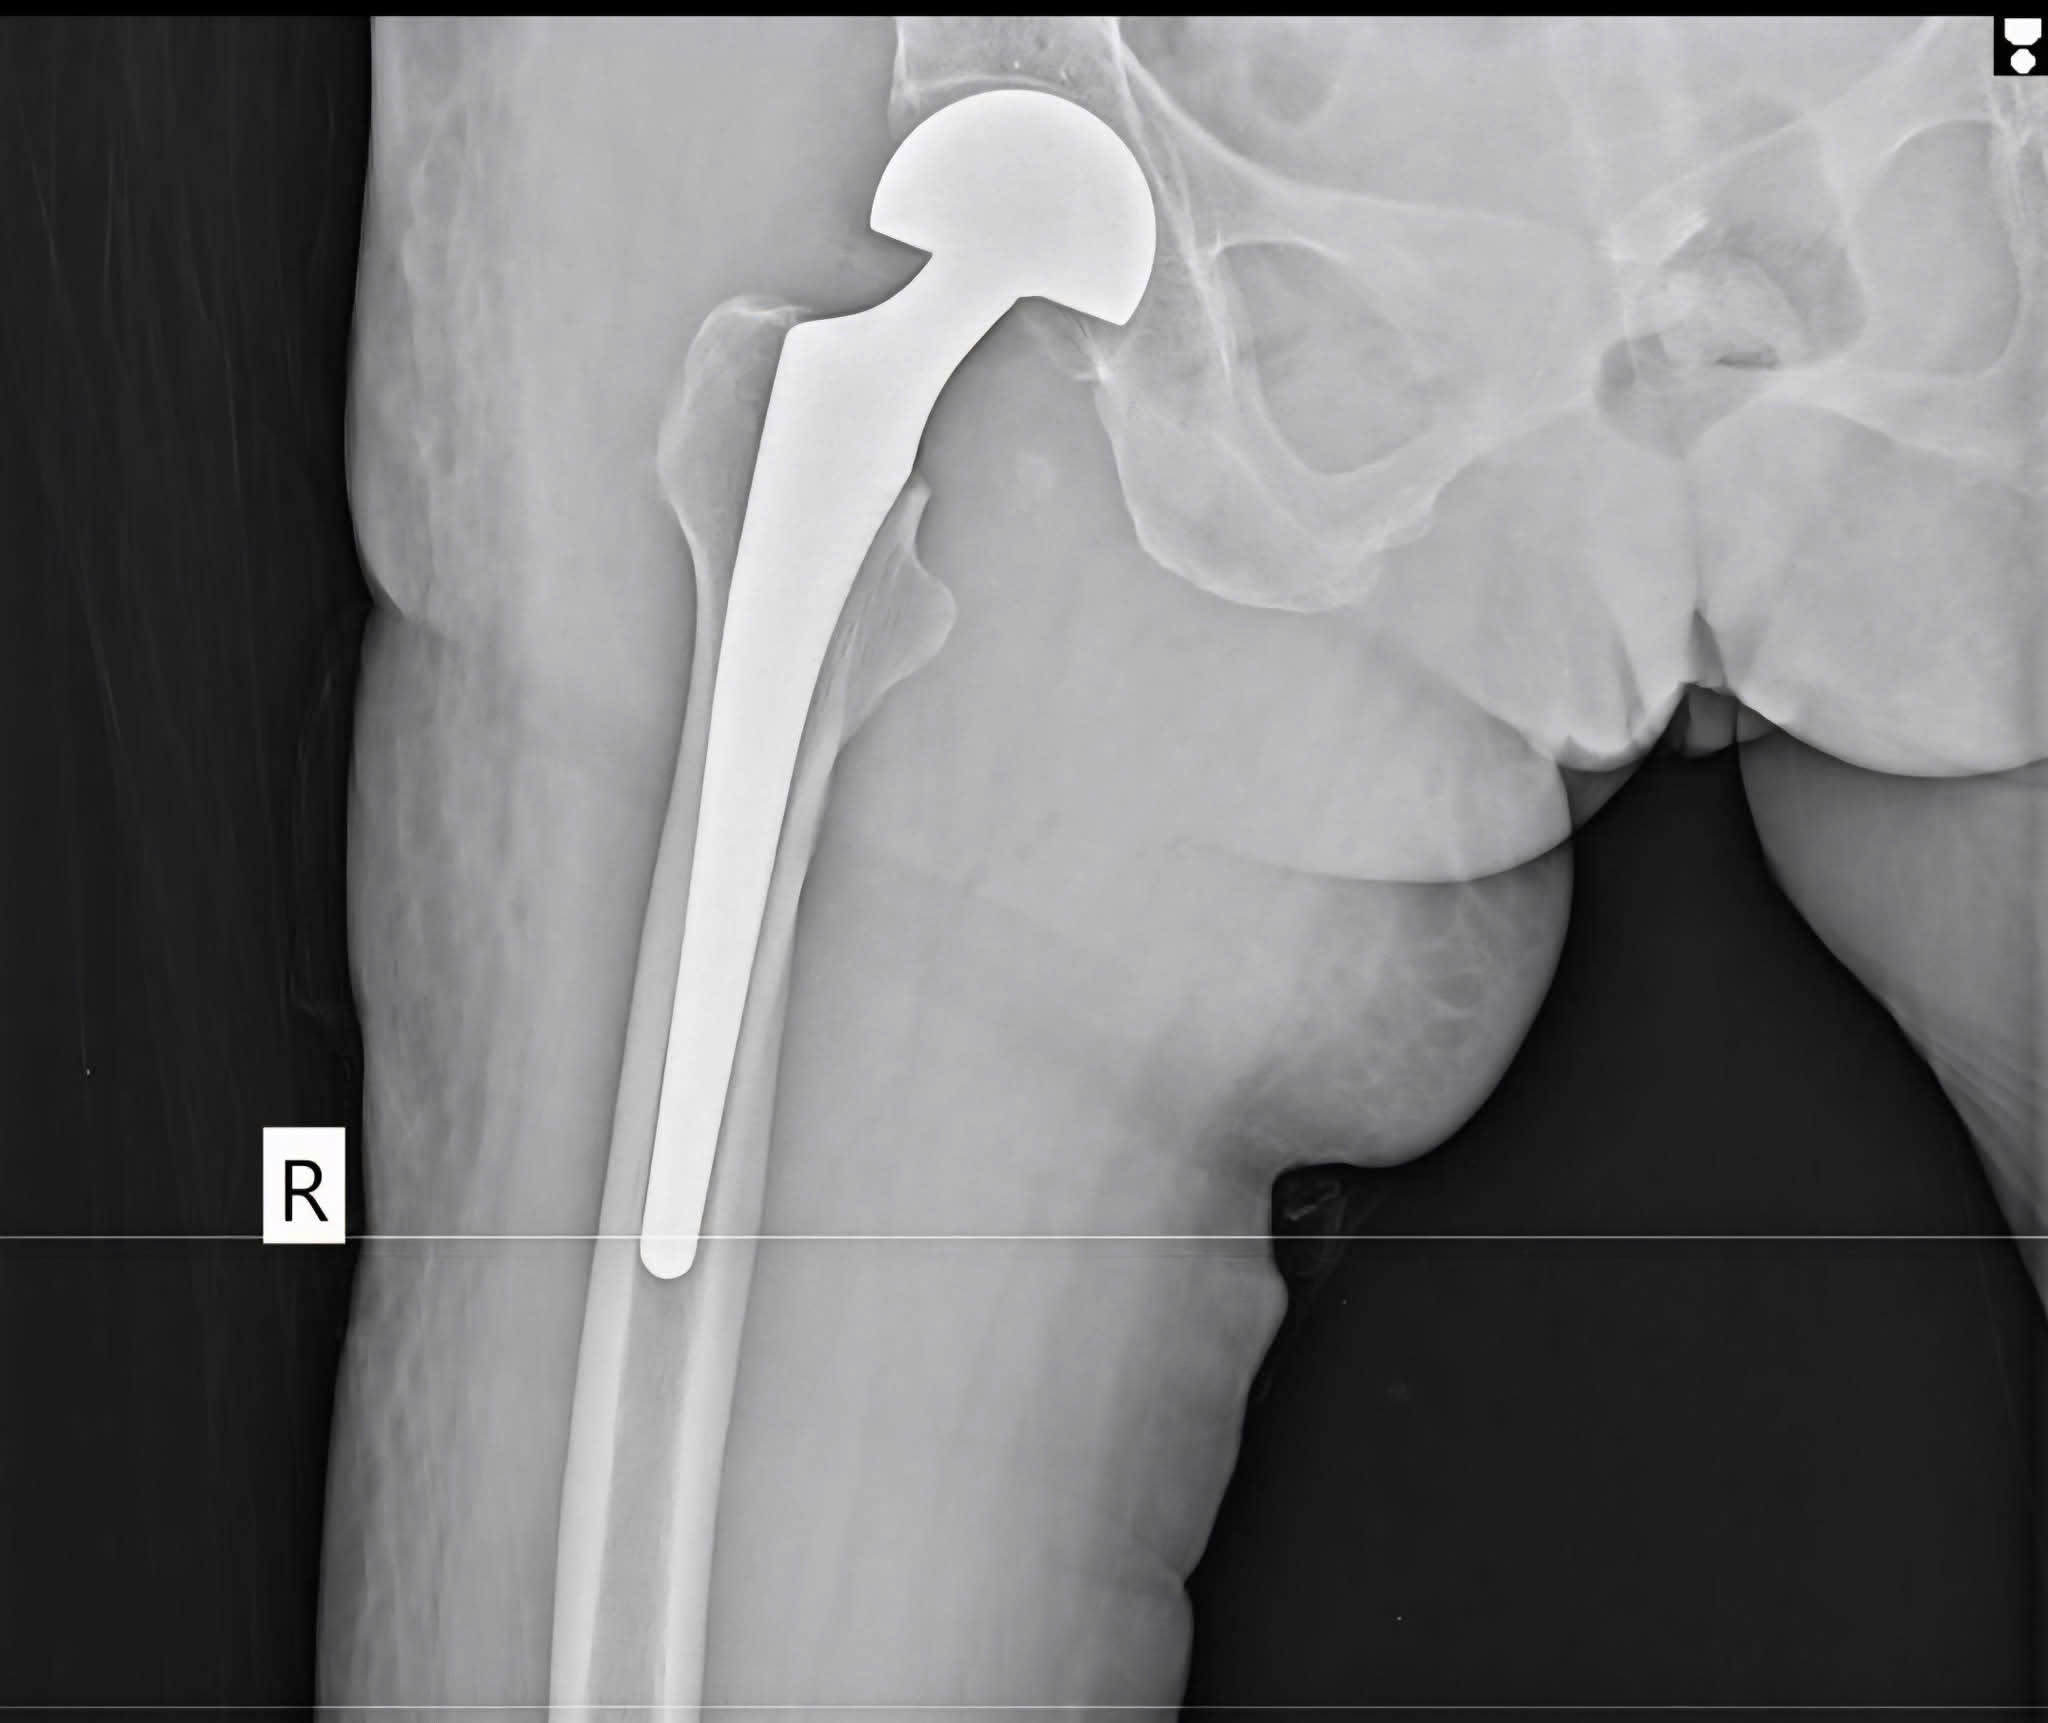

Gãy cổ xương đùi bên phải, Sau mổ thay khớp háng nhân tạo bán phần bên phải. Bệnh nhân bớt đau nhiều, có thể tự ngồi dậy sẽ tập đi lại trong vài ngày tới

Bệnh nhân nữ 74 tuổi gãy cổ xương đùi bên phải do té ngã và Sau mổ thay khớp háng nhân tạo bán phần bên phải. Bệnh nhân bớt đau nhiều, có thể tự ngồi dậy sẽ tập đi lại trong vài ngày tới